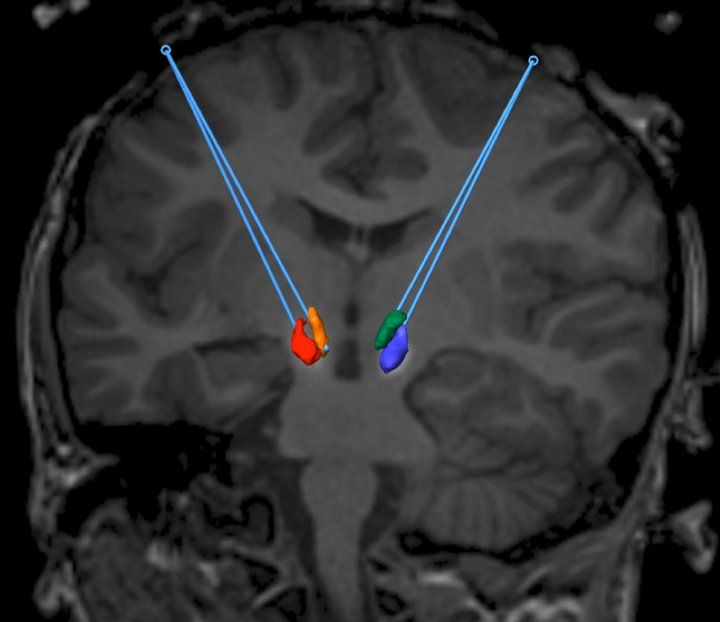

Brain image showing location of AADC targets

A corrected gene is placed in the midbrain of a patient with AADC deficiency. Image credit: UCSF

While the Parkinson’s trial focused on the putamen, a part of the brain that plays a key role in this degeneration, Gupta said the AADC gene therapy trial targeted neurons in the substantia nigra and ventral tegmental area of the brainstem, sites that may have more therapeutic benefits.